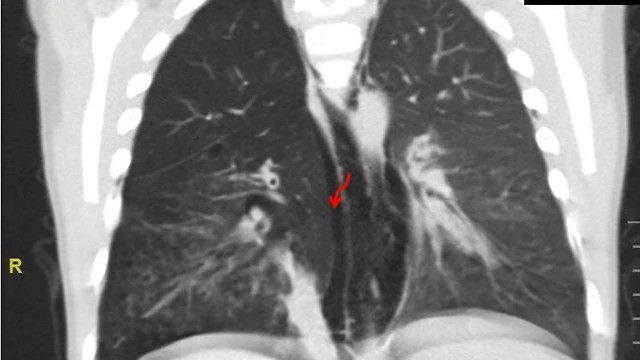

במהלך הבירור הראשוני, הועלה חשד גבוה לשאיפת גוף זר שהסתבכה וגרמה לקרע של קנה הנשימה. בבדיקת CT של החזה הודגם גוף זר חוסם, דליפה של אוויר אל מחוץ לדרכי הנשימה וכן, קרע של קנה הנשימה שנוצר עקב התהליך הדלקתי והימצאות הגוף הזר בריאותיו.

במקביל לשליפת חלקי הצנובר, הכניס ד"ר דיויד קנז, כירורג בכיר במחלקה לרפואה דחופה, נקז חזה לשחרור האוויר שהצטבר בסמוך לריאה. לאחר הניתוח הפעוט הועבר מונשם ומורדם ליחידה לטיפול נמרץ בילדים. הפעוט התאושש בצורה מלאה ושוחרר לביתו לאחר מספר ימי השגחה. צילומי מעקב הראו החלמה מלאה של הנזק הריאתי, וסגירה של הקרע.